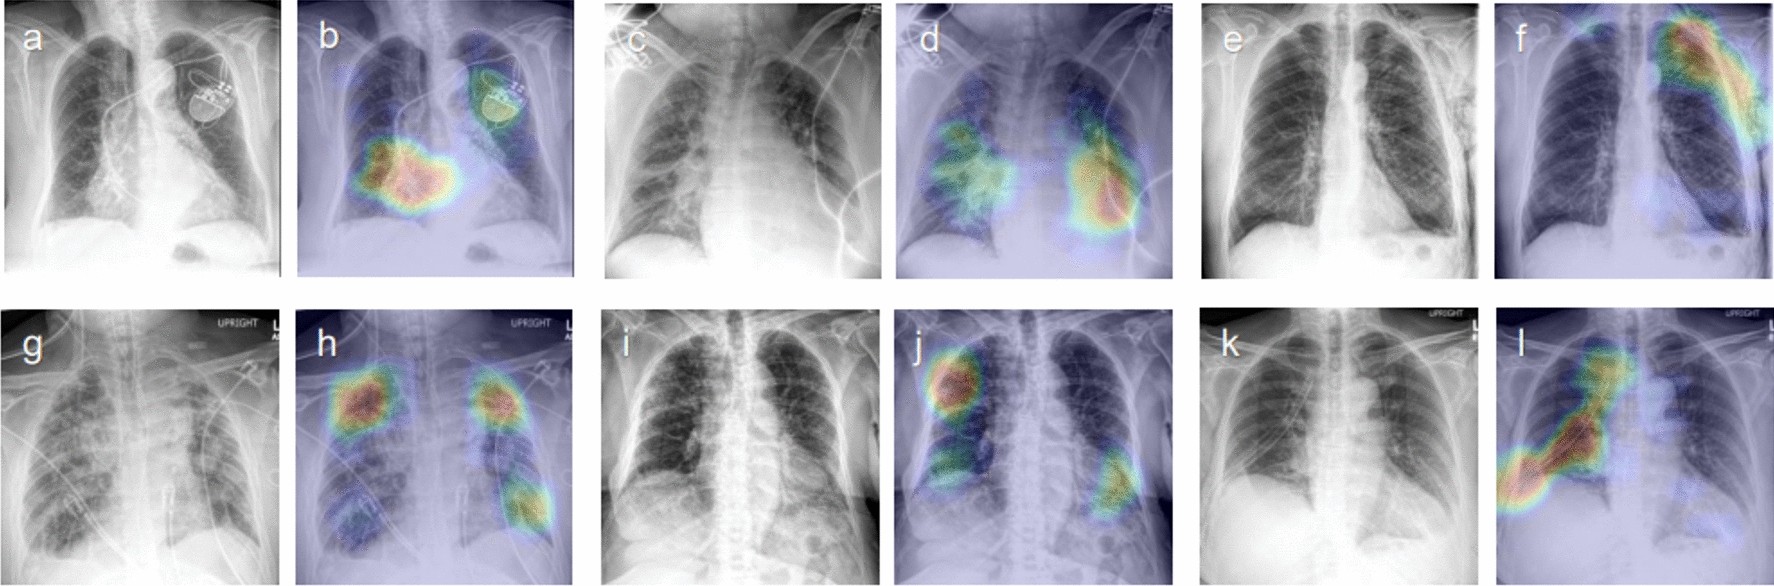

Figure 2

Representative class activation maps (CAMs) with incorrect lesion localization. (a,b) Cardiomegaly (PA), (c,d) Cardiomegaly (AP), (e,f) Pneumothorax (PA), (g,h) Other interstitial opacity (AP), (i,j) Other interstitial opacity (AP), (k,l) Pneumothorax (AP). (b) Attention map captures the tip and body of the implantable cardioverter defibrillator (ICD) rather than the enlarged heart, (d) Attention map captures pulmonary edema along with the enlarged outline of heart in cardiomegaly, (f) Attention map captures subcutaneous emphysema along with pneumothorax, (h,j) Attention map failed to capture the full area of diffuse interstitial opacities, (i) Attention map captures chest tube instead of pneumothorax.